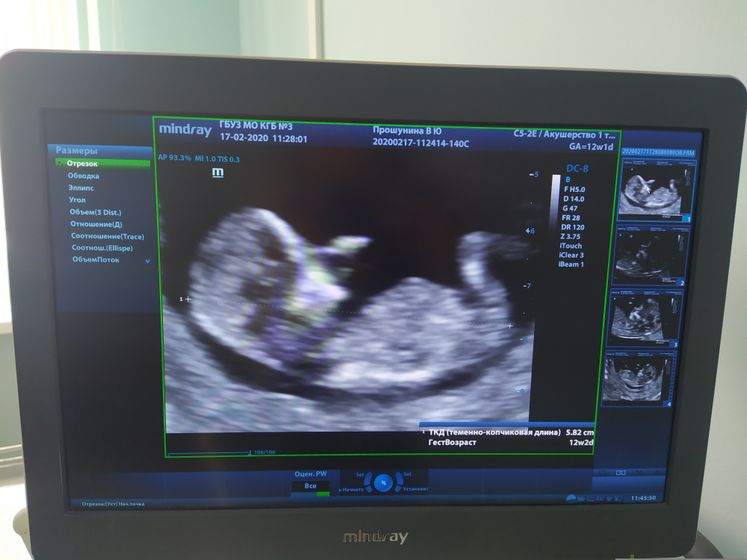

17.02 прошел наш первый скрининг, наконец то увиделись с нашей крошкой?Развиваемся нормально, все на месте, пороков нет, это самое главное ?Узи делают так долго, что успеешь понервничать ?Но это конечно того стоит ?И самое главное бьется сердечко, это походу теперь моя фобия ?И сдала кровь, надеюсь в течение недели не позвонят ?Замеры: срок 12.1 КТР 58.2 Сердцебиение 153 у/м?ТВП 1,4 Носовая кость 2,0 Преим.локак.хориона Передняя, в области внутреннего зева?И предположили пол, мальчик ?Муж конечно очень рад, но я почему то рассчитываю на девочку, мы и от первой вещи собирали, дочку на сестрёнку настраивали, да и что с мальчиками делать??? ?На каких сроках можно точно узнать пол??)